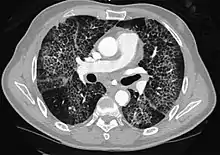

CT image showing diffuse GGOs throughout both lungs. An abscess is also noted in the right lung (screen left). - Adenocarcinoma in situ of the lung